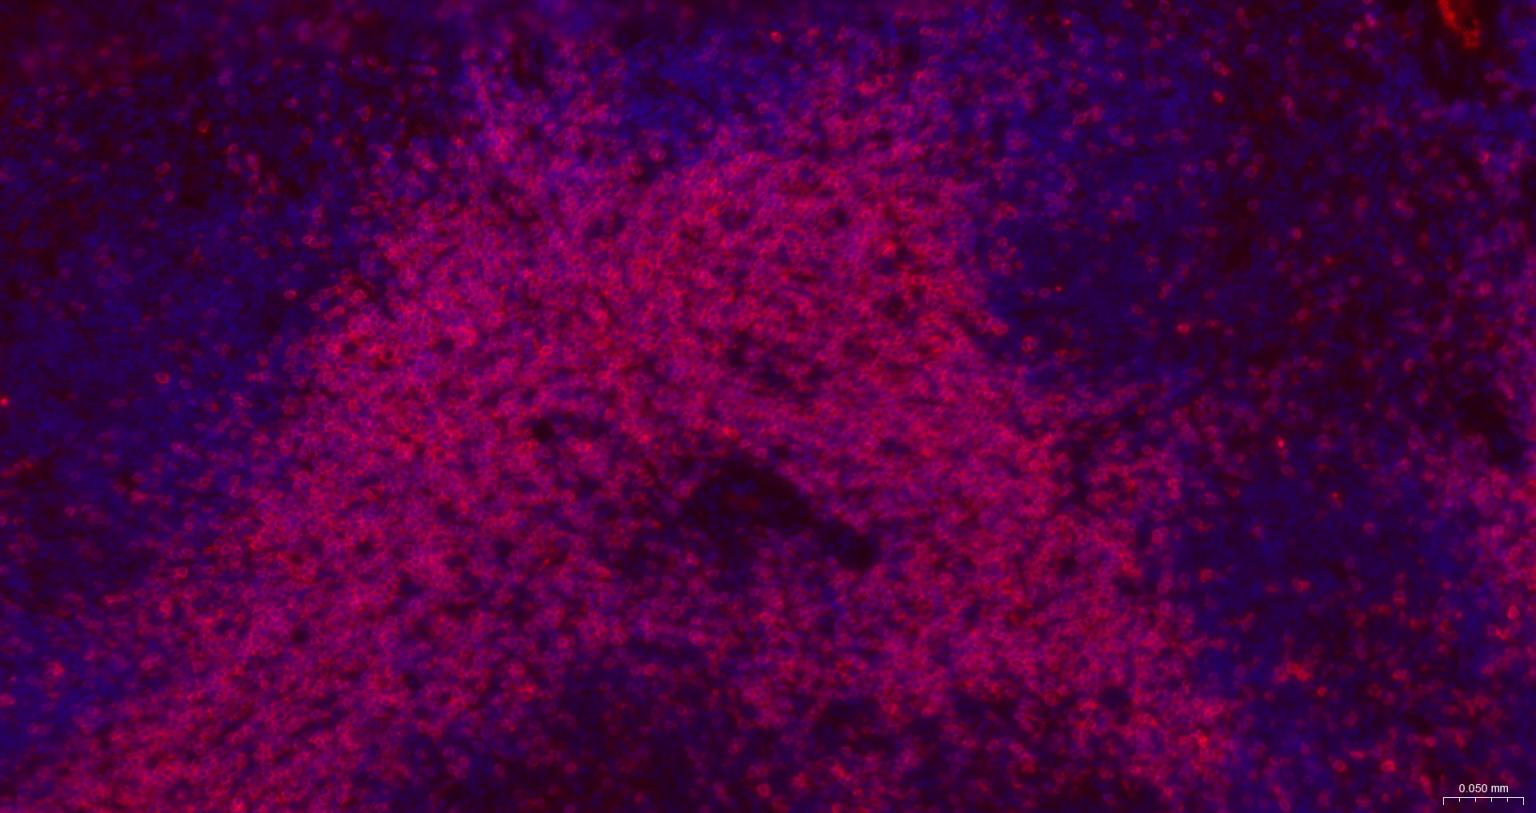

IFHuman, Mouse, Rat1:500-2000